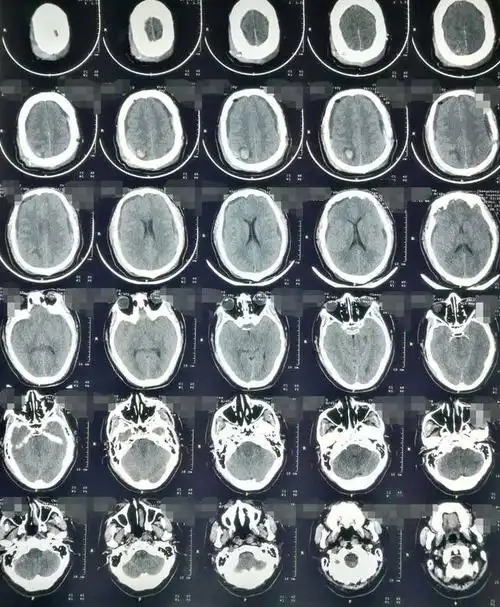

67超急性期大面积脑梗死ct平扫表现

相关图片

值班必备 | 急诊颅脑ct常见的八种疾病

影像总结头颅ct基本知识与常见病变